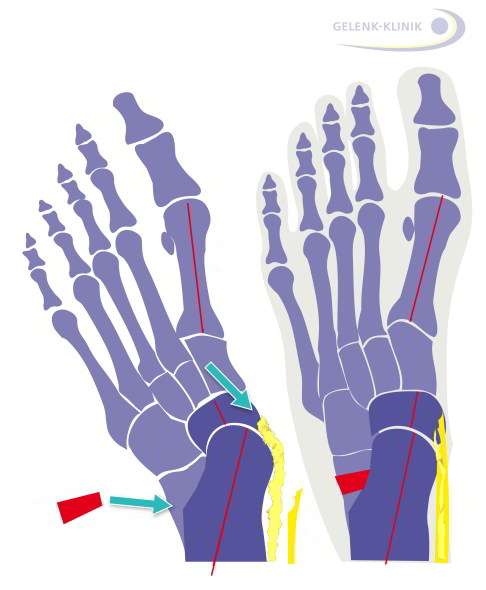

Häufig verschleißt die Tibialis-posterior-Sehne zwischen ihrem Ansatzpunkt am Kahnbein (Os naviculare) und dem Innenknöchel. Dadurch verschiebt sich die Sehnenschlinge, die das Fußgewölbe stützt, nach unten. Der außen ansetzende Wadenbeinmuskel wirkt weiterhin auf den Fuß ein, wodurch das Fußlängsgewölbe absinkt und Mittel- und Vorfuß nach außen gleiten.

Ist die Sehne schwerer geschädigt, kann ein körpereigenes (autologes) Sehnentransplantat sie ersetzen. Da das Transplantat die ursprüngliche Sehnenfunktion nur teilweise wiederherstellt, führt der Operateur zusätzlich einen knöchernen Begleiteingriff durch.

Eine Möglichkeit ist die Verlängerung des Fußaußenrandes (Evans-Osteotomie) mit Knochenteilen aus dem Beckenkamm oder Wadenbein des Patienten. So kann das Fußlängsgewölbe wieder aufgerichtet und der Sehnenzug entlastet werden. In einigen Fällen wird zusätzlich eine Arthrodese (Versteifung) des Gelenks zwischen Fersenbein und Würfelbein durchgeführt.

Eine weitere Möglichkeit bietet die Umstellung des Fersenbeins nach innen (Fersenbeinosteotomie), um die Fehlstellung des Rückfußes auszugleichen.